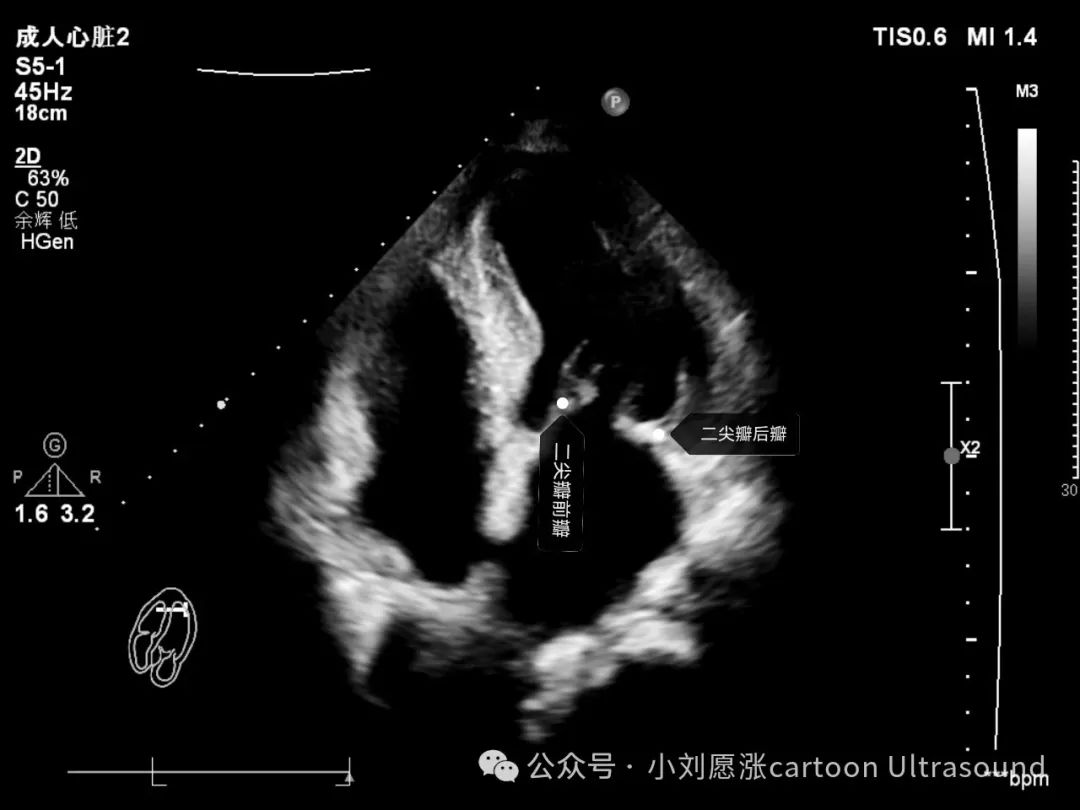

心脏超声切面 三尖瓣、二尖瓣、主动脉瓣 瓣叶识别与辨认 图片清晰易懂